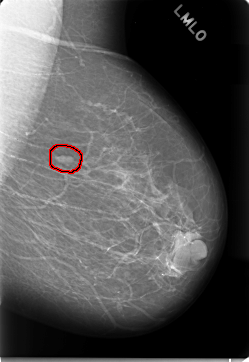

C_0019_1.LEFT_MLO

FILE: C_0019_1.LEFT_MLO.OVERLAY

TOTAL_ABNORMALITIES 1

ABNORMALITY 1

LESION_TYPE MASS SHAPE OVAL MARGINS CIRCUMSCRIBED

ASSESSMENT 2

SUBTLETY 5

PATHOLOGY BENIGN

TOTAL_OUTLINES 1

BOUNDARY